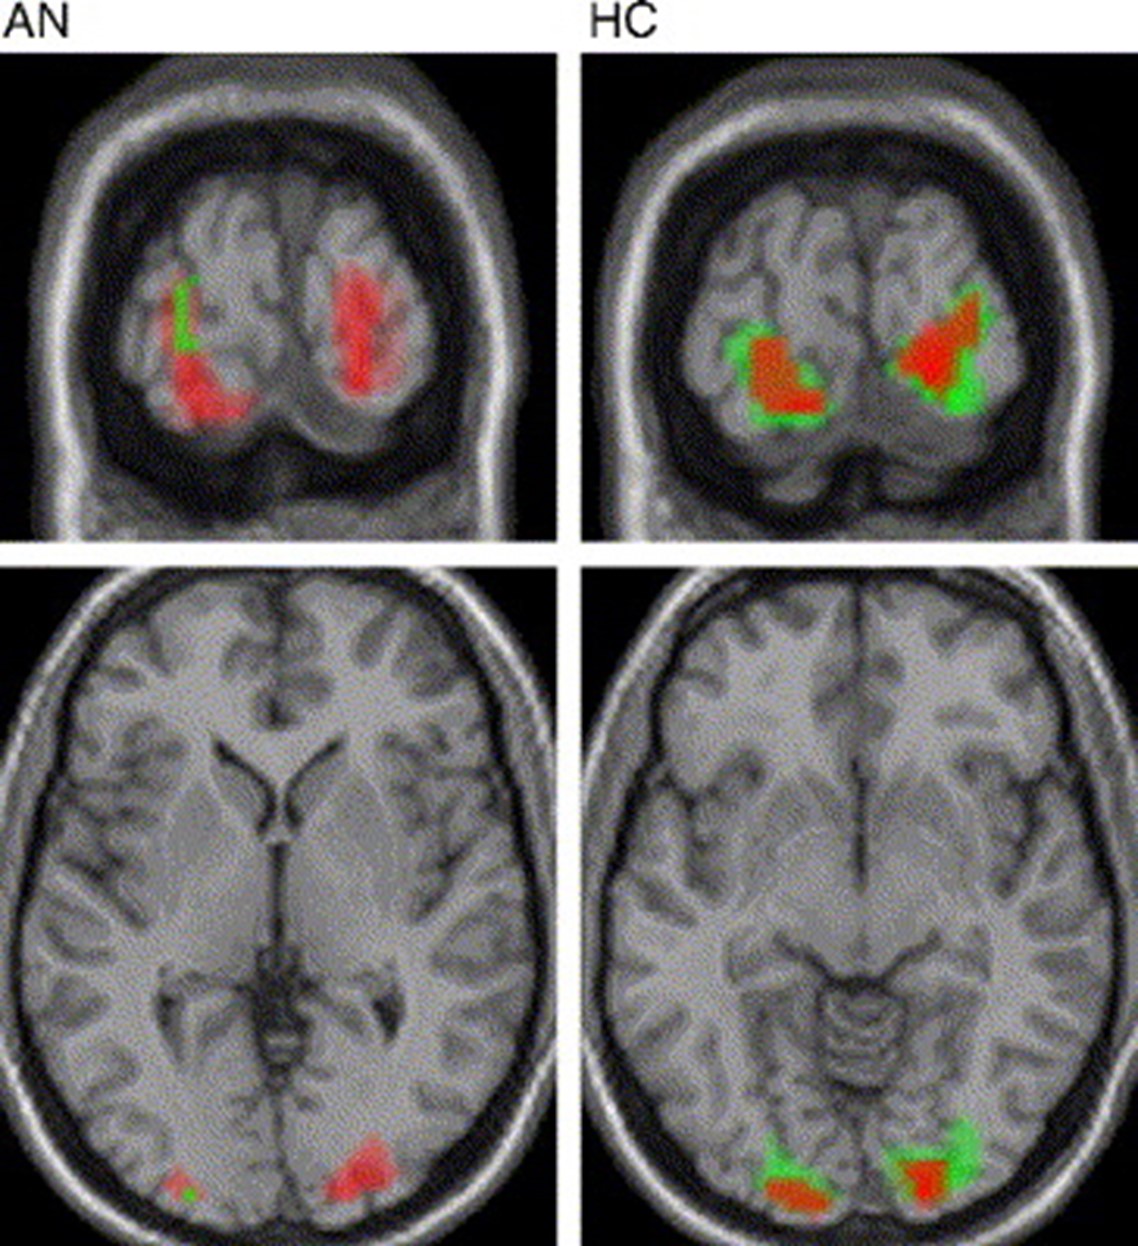

In another study 77 subjects (26 with anorexia, 25 with bulimia, 26 healthy controls) had their taste and food intake regulatory brain circuits mapped (Frank et al., 2016). The researchers wanted to find out whether there were differences in the white matter connectivity of people suffering from eating disorders and healthy controls.

The food regulatory circuit in the brain involves the hypothalamus, insula, midbrain, and prefrontal/orbitofrontal cortex (Frank et al., 2016). This study used diffusion weighted imaging and an fMRI task. For brevity’s sake, we will only discuss the diffusion weighted imaging results. A computer program was used to “generate the most probable connectivity distribution,” and people with BN and AN had higher white matter connectivity between their insula and prefrontal cortex regions (Frank et al., 2016). Also, there was less connectivity between the food-intake circuit brain regions and the hypothalamus. The imaging (fig. 2) revealed that AN and BN patients had more connectivity between their insula, orbitofrontal cortex and ventral striatum.

Furthermore, participants with these eating disorders also had less connectivity between their amygdala and orbitofrontal cortex to their hypothalamus (Frank et al., 2016). This research is important because it reveals that the hypothalamus is also involved in the brain circuitry changes of those with eating disorders. AN and BN are not just due to changes in connections between the insula, orbitofrontal cortex, and ventral striatum (Frank et al., 2016). In addition, this study showed how connectivity between the middle orbitofrontal cortex and insula positively correlated the subject’s perception of sweetness in both controls and those with eating disorders, although this was related to the fMRI task that was not discussed (Frank et al., 2016).

Figure 2- Brain connectivity patterns of AN, BN and healthy participants of study.